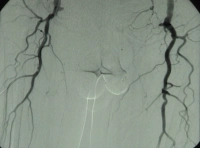

Filmbeispiel: TASC D → offene Rekonstruktion

AVK Stadium IV rechtes Bein, Stadium III linkes Bein mit:

- hochgradiger Arteriosklerose der terminalen Aorta und Beckenstrombahn bds.

- langstreckigem Verschluss der A. femoralis superficialis bds.

- Teilverschlüssen der Unterschenkelarterien bds.

Präoperative DSA des Patienten: